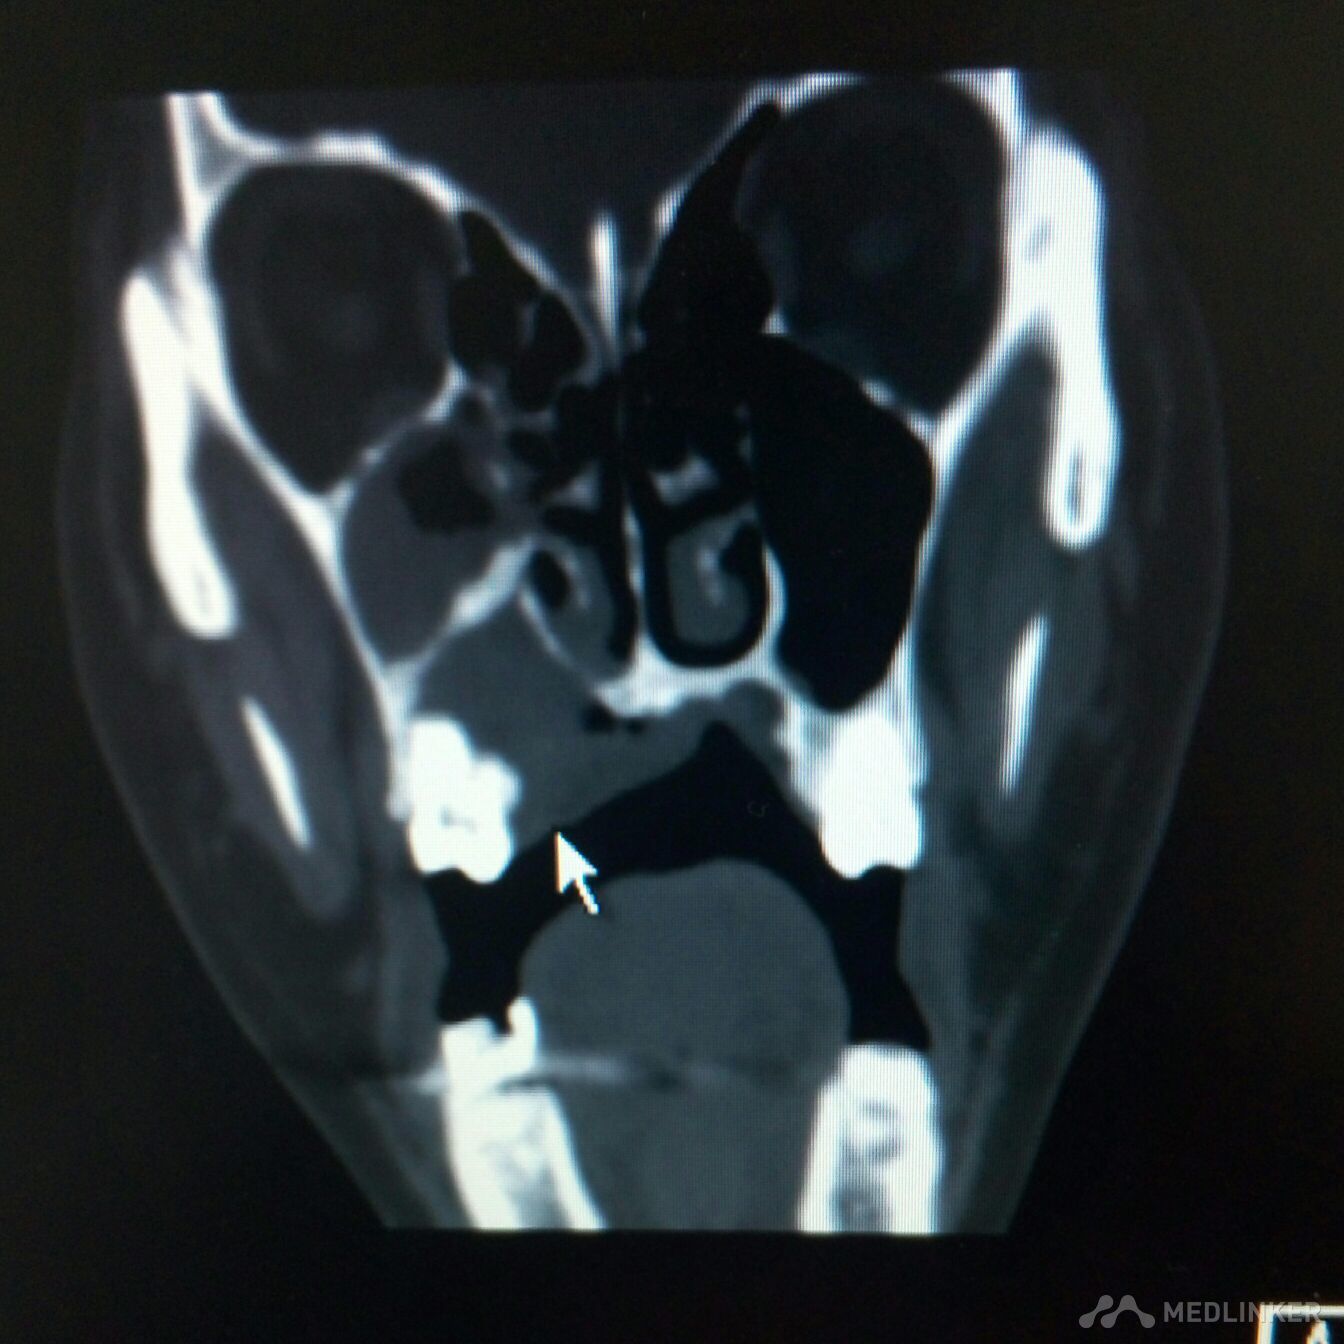

右侧上颌骨肿物,波及上颌窦,鼻腔。手术方案??

患者,女,38岁。因“发现右侧腭部肿痛一周”,来诊。查体:颌面部对称,张口度好。腭部右侧可见粘膜凸起肿物,约2*3cm,近中线处溃烂,有溢脓。CT检查可见肿物突入上颌窦及鼻腔,骨质破坏。现应用抗菌素治疗。拟行病理活检。请同仁看看手术方案?患者年轻,一侧上颌骨去除,假体如何修复?可否请鼻科联合手术,保留颌骨?